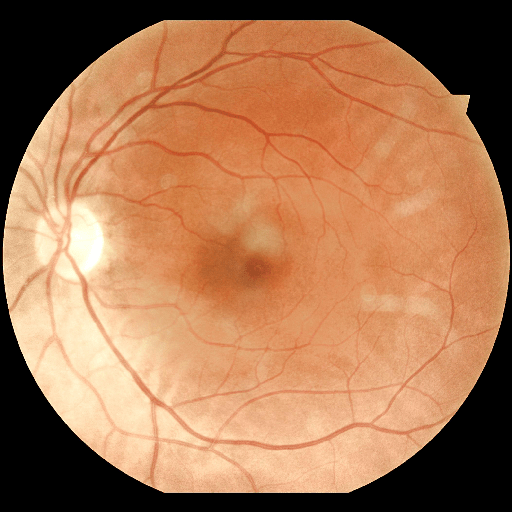

We conducted a case study on diagnosing diabetic retinopathy with ensembles of DL models. For benchmarking the performance of our ensemble-based solutions under the scheme described in Sec.3.3, we used two popular collections of diabetic retinopathy image data, the Kaggle Diabetic Retinopathy dataset [22] (hereafter referred to as “Kaggle-DR”) and the Messidor-2 dataset [23], each respectively consisting of and high resolution images. Diabetic retinopathy is graded into five SLs, as displayed in Figure 2. Following the problem setup used in previous papers [24], we trained models to distinguish the referable (SL2-4) cases from the non-referable ones (SL0 & SL1) (see Section B.1 for more detailed descriptions). We also tested our trained ensemble models on two o.o.d. image datasets (ImageNet [25] and CIFAR-10 [26]) to examine their capabilities of identifying o.o.d. inputs (see Section B in the supplementary materials).

5.1 Distribution of Uncertainty Scores

Distribution of Uncertainty Scores Across Different Severity Levels As explained in Section 3, each uncertainty metric essentially defines an order/ranking among the data points. We conducted an analysis to better understand what data will be assigned high uncertainty under a particular uncertainty metric . Picking out the highest ranked data points (), we calculated the ratio of data points from each SL. Figure 4 summarizes the results as box plots for the Kaggle-DR and the Messidor-2 datasets; additional detailed statistics can be found in Table S.1 in the supplementary materials. From the plot and table, SL1 & SL2 examples account for a higher proportion among the top-ranked uncertain examples across the three ensemble methods. This finding matches our intuition that incipient disease examples (SL1 & SL2) are more likely to be considered uncertain by ensemble methods due to their ambiguity.

The Kaggle-DR dataset comprises high resolution images. The presence of diabetic retinopathy is rated into five different SLs: no-DR (SL0), mild (SL1), moderate (SL2), severe (SL3), and proliferate (SL4), as illustrated in Figure 2. We divided the Kaggle-DR dataset into a development set and a test set, which respectively consisted of and images. The data in the development set were used to train and validate our Deep Learning (DL) models. The Messidor-2 dataset [38] that consisted of images was also used in our experiment as an additional dataset to test the true generalization performance of the models trained on the Kaggle-DR dataset. Images in Messidor-2 dataset were graded into the five SLs as in the Kaggle-DR dataset. Figure S.1 provides an illustration of the datasets used in our experiments.

The image data used in our experiment were all unified into square-shaped images with resolutions or in our preprocessing procedures. For training each neural network model, only images of the same resolution were used. The original images came with either of the two forms as exemplified in Figure S.2. In the first form (Figure 2(a)), the entire fundus was visible in the image. We cropped the image such that the fundus was tightly fitted inside the square. In the second form of input images shown in Figure 2(b), part of the fundus was not visible. We padded blank strips to make the image square-shaped and in a unified resolution. See the provided code for further details.